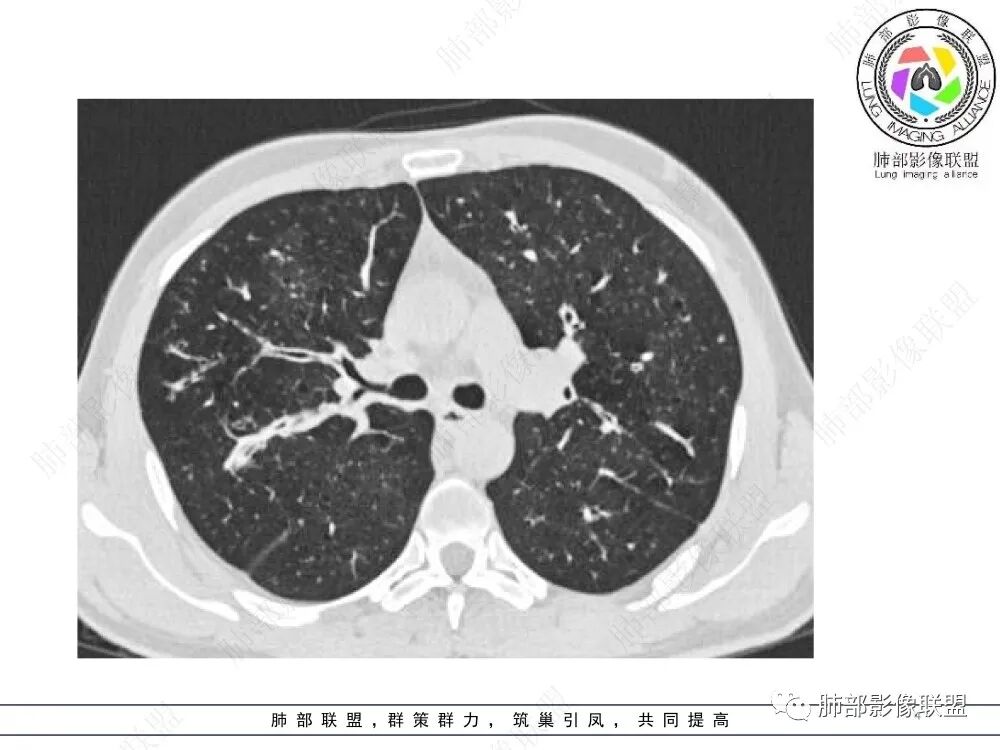

中年男性,慢性咳嗽,有吸烟史,胸部CT基础尚可,双肺多发的沿支气管播散的树芽影以及支气管管壁的增厚和对应区域内的斑片影实变影,符合气道播散的表现。经过对症抗感染治疗1月之后,胸部CT影像进展。右侧播散到左侧。实变和漱牙以及气管壁增厚均较前明显进展。

35岁男性,慢性咳嗽2月余,吸烟17年。弥漫支气管壁增厚,腔部分增宽,部分狭窄,远端粘液栓,树芽征,边界模糊,抗炎无效。

6/13复查,外围出现斑片状实变影,周围GGO,从发病过程:支气管壁增厚,延续到小气道炎症,然后周围实变,首先气道来源病变,因为支气管壁的增厚,腔狭窄、扩张,其次病变广泛,几乎累及所有叶段,常规思路:气道侵袭性曲霉菌病;不除外努卡。与NTM鉴别,NTM其实支气管扩张为中型的多为中外带支气管扩张,中近端支气管改变不明显,这个中内带明显,而且早期是中内带为主。

2.胸部CT:两肺广泛的支扩,支气管壁增厚,多发的树芽影,部分伴有支气管周围的渗出,少量实变。不足一月复查,原有支扩、支气管壁增厚基础上伴有大量渗出,实变,结节,胸膜下累及。

3.综合分析:首先病灶沿支气管分布,呈树芽征及实变影,相应支气管壁广泛增厚,其次病变范围比较广泛,几乎累及所有叶段,这种表现常高度提示气道播散,经过对症抗感染治疗20多天后,胸部CT影像明显进展。符合IPA的进展表现。